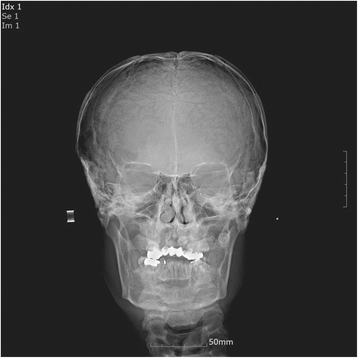

La displasia cleidocraneal es una condición genética poco común que afecta el desarrollo de los huesos del cráneo y los hombros. Se caracteriza por el retraso en el cierre de las fontanelas del bebé, mentón y frente prominentes, nariz ancha, paladar alto, clavículas cortas o ausentes, hombros estrechos y flexibles, baja estatura, retraso en el crecimiento dental y una mayor cantidad de dientes. Esta condición puede ser diagnosticada por un pediatra que observa estas características físicas y puede requerir pruebas como radiografías y análisis genéticos para confirmar el diagnóstico.

Algunos pacientes con displasia cleidocraneal pueden experimentar problemas dentales, como dientes adicionales, dientes mal alineados o un paladar anormalmente alto. En estos casos, se puede consultar a un dentista u ortodoncista para evaluar la necesidad de aplicar algún tipo de aparatología dental o llevar a cabo una cirugía con el objetivo de mejorar la apariencia de la boca y facilitar la masticación adecuada de los alimentos.

Sí, la displasia cleidocraneal afecta el desarrollo de los huesos del cráneo y los hombros. Las clavículas pueden ser cortas o estar ausentes, lo que afecta la estructura de los hombros. Además, puede haber retraso en el cierre de las fontanelas del bebé y en el desarrollo dental.

La displasia cleidocraneal es una condición genética que afecta el desarrollo de los huesos del cráneo y los hombros. Se caracteriza por síntomas como el retraso en el cierre de las fontanelas, el mentón y la frente prominentes, y alteraciones dentales. El diagnóstico se realiza a través de la observación de las características físicas y puede requerir pruebas adicionales, como radiografías y análisis genéticos. Aunque no existe una cura para la displasia cleidocraneal, hay opciones de tratamiento disponibles para abordar las alteraciones específicas y mejorar la calidad de vida del paciente. Además, es importante contar con el apoyo de organizaciones y recursos especializados para obtener información y apoyo emocional.